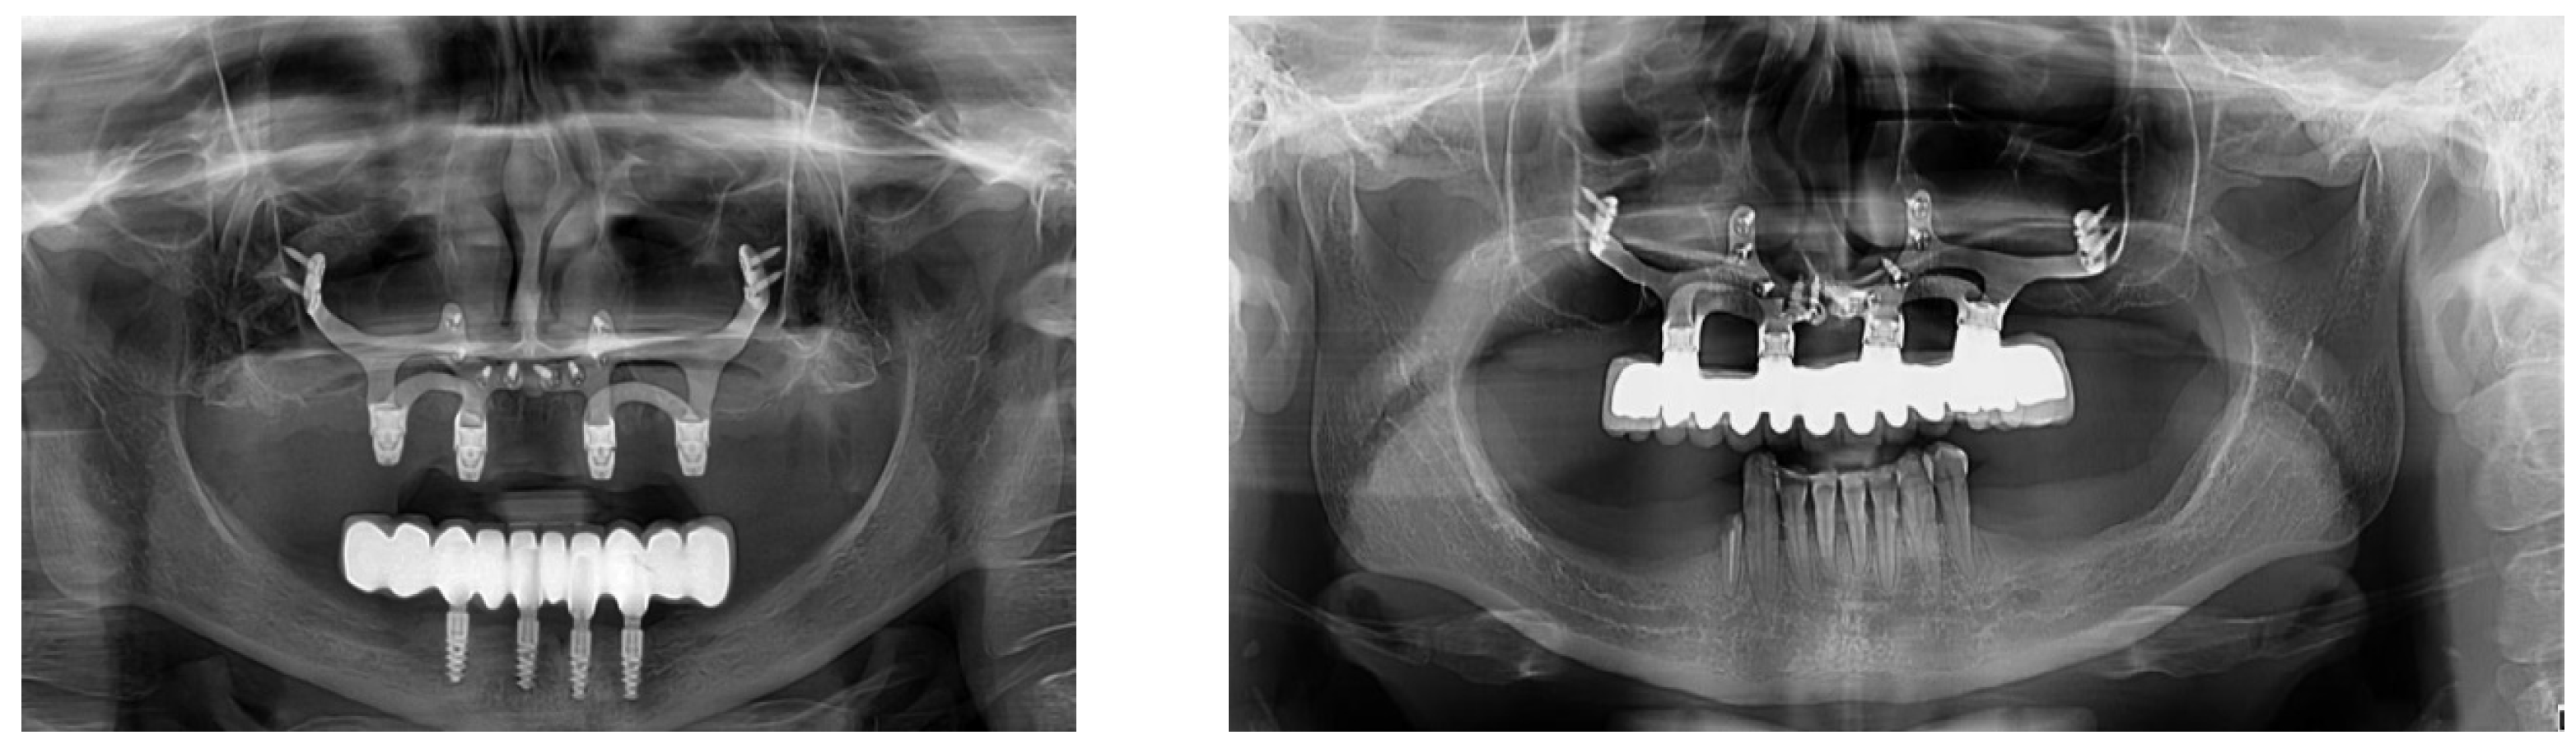

2.3. Design and Production of Patient-Specific Subperiostal Implants

2.4. Surgical Procedure and Prosthetic Treatment

| Location | Type | Number of Subperiosteal Structures | Number of Struts |

|---|---|---|---|

| Maxillary | Full arch | 26 | 3 struts on a hemiarch |

| 20 | 2 struts on a hemiarch | ||

| Partial Uniterminal arch | 2 | 2 struts | |

| Mandibular | Partial Biterminal arch | 2 (×2) | 2 struts on a hemiarch |

| Partial Uniterminal arch | 9 | 2 struts |